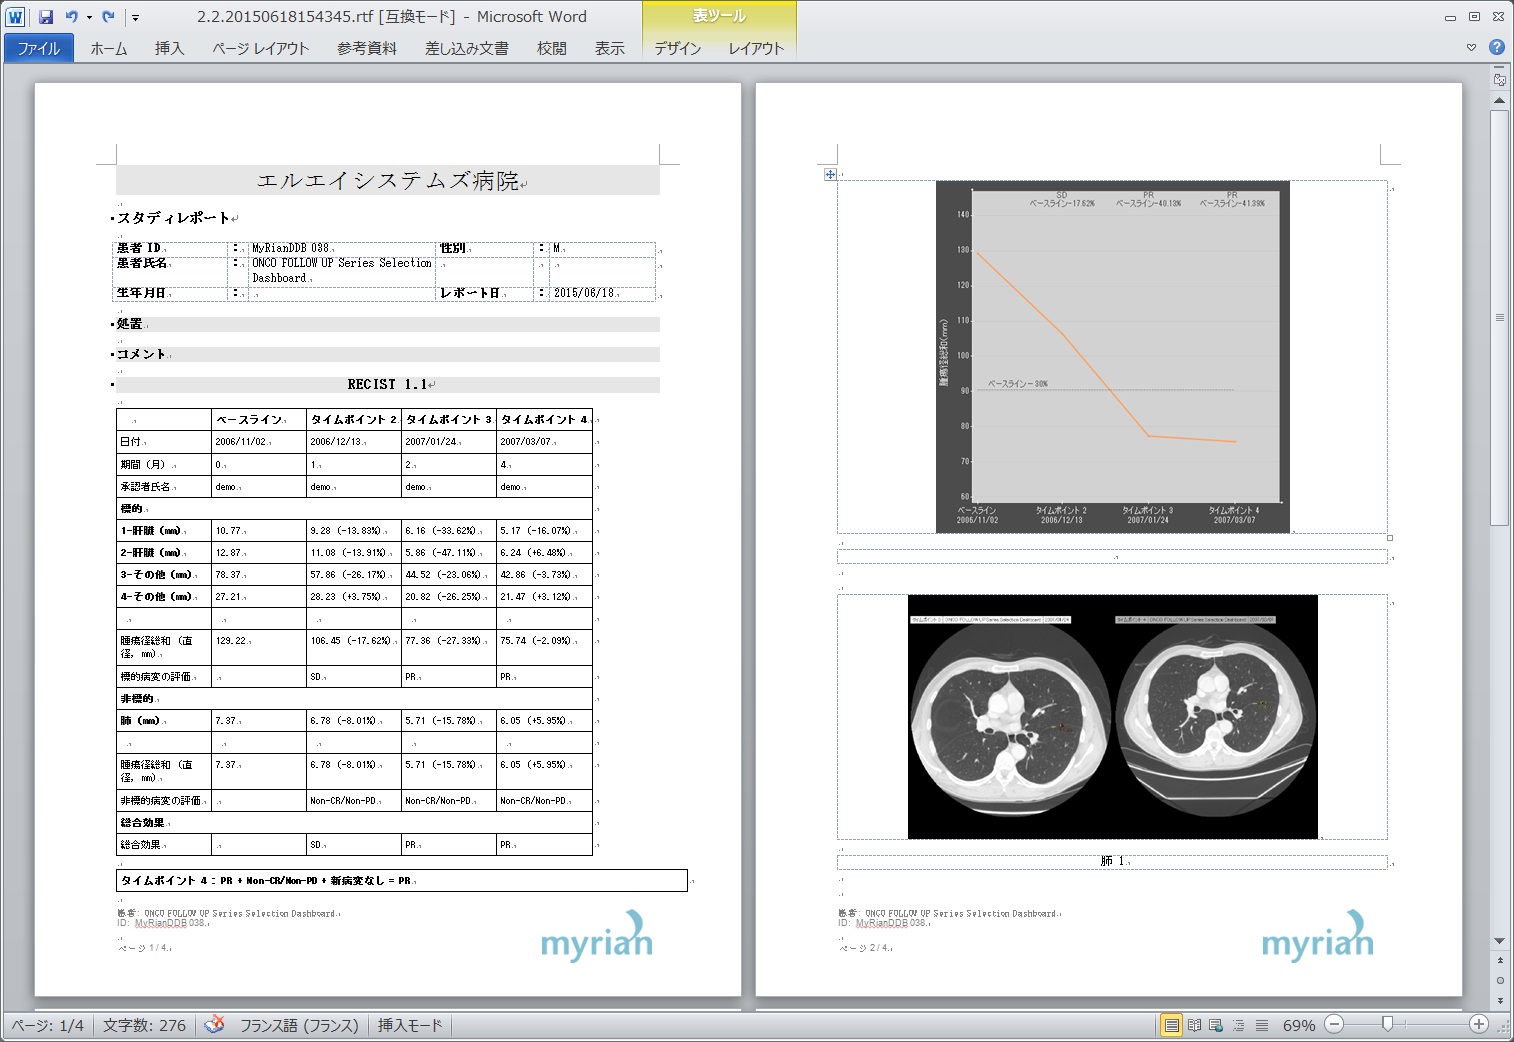

Myrian®XL-Onco 腫瘍の経時的フォローアップ・アプリケーション

効率的なフォローアップのための理想的なソフトウェア

フォローアップに必要なすべてのステップは自動化されています。 ベースライン作成後、次のタイムポイントでは自動的に非剛体レジストレーションが行われ、高速な検査比較が可能です。必要に応じて自動で国際評価基準(RECIST1.0,1.1)に沿った治療レスポンスが計算され、PACSへ転送されます。そし検査レポートも自動作成されます。

| 5.自動作成レポート |

|---|

|

|